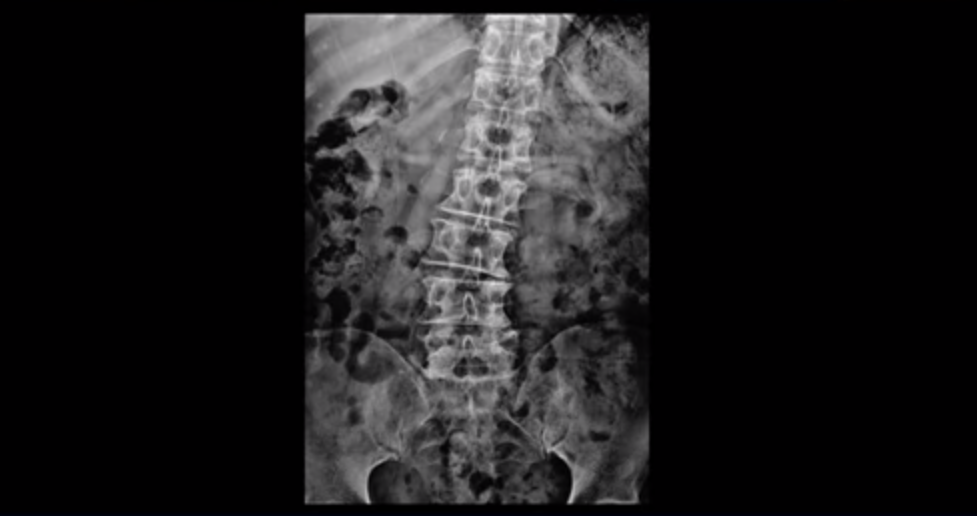

이분 X-ray를 보시면 허리가 이렇게 심하게 휘어 있습니다.

근육들이 다 약해지고 망가져서 척추를 잘 지지하지 못하니 이렇게 심하게 척추가 휘어지는 겁니다. 이렇게 근육이 안 좋으면 신경이 더 눌립니다. 이렇게 망가진 근육이 근육재활치료와 운동으로 좋아지면 허리를 더 잘 지탱하게 되니까 신경이 덜 눌립니다. 즉 협착증이 좋아지는 겁니다. 그럼 이런 근육재활치료와 운동은 어떻게 하는 걸까요? 이분 말씀 조금 더 들어본 후에 근육재활치료 모커리 ABCDE 치료법은 어떻게 하는 건지 자세히 설명 드리겠습니다.